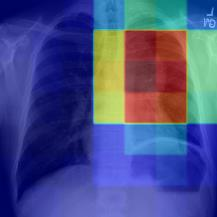

Thoracic disease detection from chest radiographs using deep learning methods has been an active area of research in the last decade. Most previous methods attempt to focus on the diseased organs of the image by identifying spatial regions responsible for significant contributions to the model's prediction. In contrast, expert radiologists first locate the prominent anatomical structures before determining if those regions are anomalous. Therefore, integrating anatomical knowledge within deep learning models could bring substantial improvement in automatic disease classification. This work proposes an anatomy-aware attention-based architecture named Anatomy X-Net, that prioritizes the spatial features guided by the pre-identified anatomy regions. We leverage a semi-supervised learning method using the JSRT dataset containing organ-level annotation to obtain the anatomical segmentation masks (for lungs and heart) for the NIH and CheXpert datasets. The proposed Anatomy X-Net uses the pre-trained DenseNet-121 as the backbone network with two corresponding structured modules, the Anatomy Aware Attention (AAA) and Probabilistic Weighted Average Pooling (PWAP), in a cohesive framework for anatomical attention learning. Our proposed method sets new state-of-the-art performance on the official NIH test set with an AUC score of 0.8439, proving the efficacy of utilizing the anatomy segmentation knowledge to improve the thoracic disease classification. Furthermore, the Anatomy X-Net yields an averaged AUC of 0.9020 on the Stanford CheXpert dataset, improving on existing methods that demonstrate the generalizability of the proposed framework.